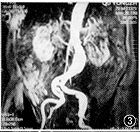

图1,2 图1为SE左前斜位,示主动脉弓部囊状突出,内无信号;图2为三维增强磁共振血管造影(3D DCE MRA)左前斜位,示左锁骨下动脉开口以远可见囊状突出,其内信号与主动脉弓相同,手术证实为假性动脉瘤 图3,4 图3为3D DCE MRA冠状位,示腹主动脉扭曲,肾动脉水平以下瘤样扩张,左肾动脉起始部局限性重度狭窄,双侧髂总动脉多发狭窄和扩张;图4 为SE轴位,示腹主动脉扩张,其内可见新月形附壁血栓,手术证实为真性动脉瘤伴附壁血栓 图5,6 图5为数字减影动脉血管造影(IADSA)冠状位,示腹主动脉扭曲延长,双肾动脉水平以下呈囊状扩张,左肾动脉起始部局限性重度狭窄,右肾动脉起始部局限性轻度狭窄;图6为3D DCE MRA冠状位,除与图5相同表现外,还可见双侧髂总动脉、髂内、外动脉多发狭窄伴扩张,管腔不规则 图7,8 图7为3D DCE MRA冠状位,示双侧髂总动脉及髂内、外动脉多发狭窄,右侧桥血管通畅,与髂总动脉吻合处轻度狭窄;图8为IADSA冠状位,除与图7相同表现外,侧支血管显示较3D DCE MRA佳

病变组34例 3D DCE MRA与IADSA或(和)手术结果对照,符合率分别为胸腹主动脉100.0%(12/12例) (图1~6),髂动脉87.5%(7/8例)(图7,8),颈动脉80.0%(4/5例),头臂动脉75.0%(3/4例),肾动脉60.0%(3/5例),总的符合率为85.3%,主动脉及其主支病变则分别为100.0%和77.3%。与IADSA或(和)手术结果对照的34例病人3D DCE MRA显示假阴性2例,16例正常组中假阳性2例,误诊率8.0%;其敏感性、特异性和准确性分别为94.1%、87.5%和92.0%。

全组中主动脉成像20例,包括主动脉瘤、主动脉夹层等16例(胸和腹主动脉分别为11和5例),其中12例有IADSA或(和)手术对照,诊断符合率100%。3D DCE MRA 同SE和梯度回波(GE),能正确显示动脉瘤瘤体大小、主动脉夹层的真假腔和内膜片,鉴别假腔内附壁血栓或慢血流,主动脉狭窄范围和程度,且3D DCE MRA显示主动脉病变与头臂和肾动脉等主支的关系优于SE和GE,可为手术提供重要信息。但不能直接显示瘤体内的附壁血栓大小、范围、主动脉管壁结构以及其与周边脏器的解剖关系,但MRI的SE或(和)GE技术能弥补其不足。因此从整体效果上3D DCE MRA对主动脉疾患的诊断可与IADSA媲美。同时本法无需动脉插管,属微创技术。